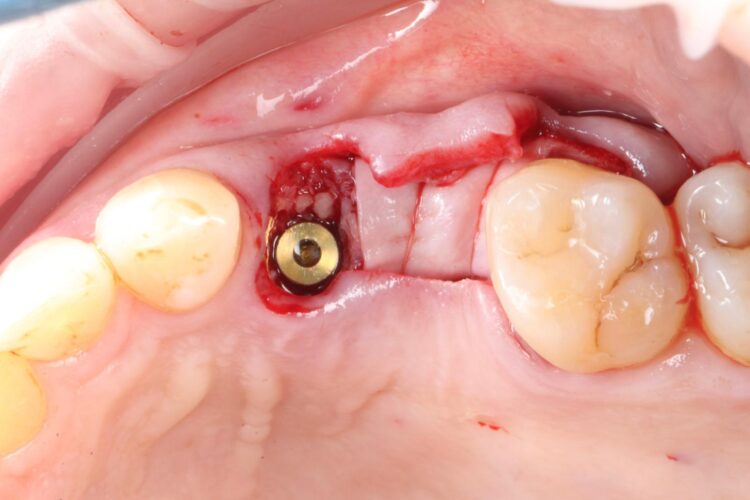

Two 3.8mm diameter CONELOG® Progressive-Line implants were placed through the guide, following the plan precisely. The UL4 implant was longer (11mm) to ensure sufficient apical bone was engaged for primary stability, it was also positioned in the palatal root to ensure good engagement with the bone and better bone to implant contact. A sizable jump gap was noted between the implant and the buccal plate of around 5-6mm. From a biological perspective, the jump gap can be left because the ridge would heal to leave a sufficient buccal plate. However, the literature[iv] shows that grafting reduces the amount of bone resorption post implant placement, which was one of the reasons that augmentation was indicated in this case.

Another predetermined concern was the amount of remaining bone surrounding an implant after placement. There was less than 2mm of residual bone buccal to the UL5 site once the implant was placed. Alberto Monje et al. (2023) [v] showed that thin buccal bone at the implant site increases the risk of major dimensional changes, this can have direct implications on the aesthetics and functional outcomes.

Consequently, the bone was contour-augmented, using MinerOss® Blend (BioHorizons Camlog), which provides a good combination of cortical and cancellous bone for efficient bone turnover and also maintains graft stability in the healing phase. The graft was held in place with a collagen membrane stabilised using resorbable sutures. The custom healing abutment is then placed and torqued (10Ncm) into the UL4 implant before the wound is approximated and sutured using a non-resorbable 6-0 Prolene suture.

An x-ray was taken immediately post-operatively to confirm that the temporary cylinder was seated correctly and wasn’t catching on the socket walls. This image also provided a reference for the custom healing abutment position and ensured that the bone graft material added to the jump gaps wasn’t preventing this abutment from fully seating.